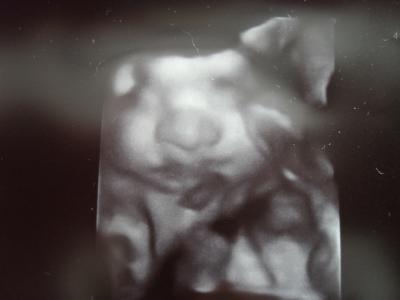

Na das ist doch grosse mädchen! Supi das es alles ok ist ! Sehr sehr schones foto !Dieses goldige nase u mund nur zum Lg Qimi

Was ist das für ein tolles Bild? Ist das nicht schon 3 D? Solche Bilder bekomme ich nie!